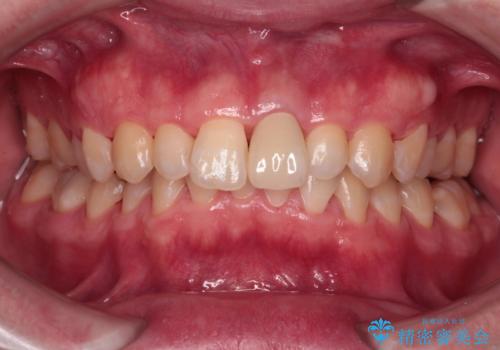

変色した前歯をオールセラミッククラウンに

- 転んだ際に欠けてしまった前歯の変色が気になるとのことで来院された患者様です。

診察やレントゲン写真より神経組織の失活が認められたため、根管治療、ファイバーコアによる土台築製後、オールセラミッククラウンにて補綴することとしました。

神経を取り除いた歯は時間とともに変色してきます。

クリーニングやホワイトニングでは改善できないため、オールセラミッククラウンなどによる補綴治療が必要となります。